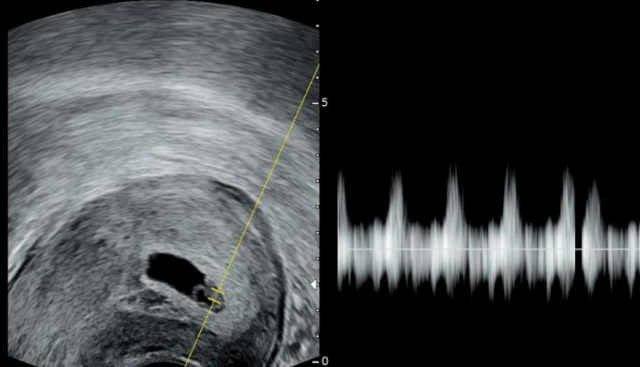

③ 태아 및 심장박동(Fetal Pole & Cardiac Activity)

6주차 중후반이 되면

태아 모습(0.5~1cm)과 함께 심장박동이 관찰될 수 있습니다.

깜빡이는 모습으로 보이다가,

이후 청진기로 심장소리를 직접 들을 수 있는 단계로 넘어갑니다.

심장박동은 평균적으로 임신 6주~6주 후반부터 확인됩니다.